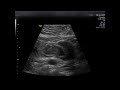

Обзор: Узи мурманск Здесь я решила рассмотреть хорошо ли выполняются услуги УЗИ в медицинском центре "Губернский Лекарь"

Рассмотрена медицинская клиника. Узи мурманск

Сначала рассмотрим медицинский центр "Губернский Лекарь". Лично мне очень понравился персонал, хорошие врачи, отлично выполняют различные медицинские услуги, включая УЗИ. Цены не кусаются.

Очень порадовало умение врачей не только выполнять свою работу, но и умение вести диалог, не выходя за рамки дозволенного и этики. Обстановка в клинике: уютный интерьер, чистота, как в кабинете, так и в коридорах. Этот центр представляет различные виды УЗИ, например:УЗИ органов брюшной полости (печень, желчный пузырь, поджелудочная железа, селезенка), УЗИ печени, желчного пузыря, поджелудочной железы, почек, УЗИ печени с доплерографией сосудов, УЗИ селезенки с доплерографией, УЗИ лимфоузлов, УЗИ надпочечников, УЗИ желудка с определением моторно-эвакуаторной функции, УЗИ: мягкие ткани + регионарные лимфоузлы, УЗИ: забрюшнное пространство, УЗИ: почки, мочевой пузырь, предстательная железа, остаточная моча, органы мошонки, УЗИ органов малого таза (гинекологическое), УЗИ одноименных суставов конечностей (тазобедренные, коленные, локтевые, лучезапястные и т. д.), УЗИ вилочковой железы, УЗИ плевры и плевральной полости, УЗИ брюшного отдела аорты и подвздошных артерий. Сходите, не пожалеете. Сейчас там действуют различные акции, так что вы сможете ещё и сэкономить. Не забывайте о своём здоровье!